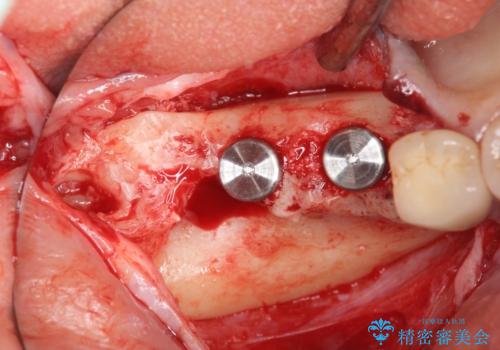

インプラントの埋入には十分な骨量が必要ですが、虫食い状に骨が足りなかった為インプラントの埋入と同時に骨の増成を行いました。

インプラントを埋入する手術と同時に骨の増成を行う場合と、埋入前に骨の造成だけを行う場合があります。